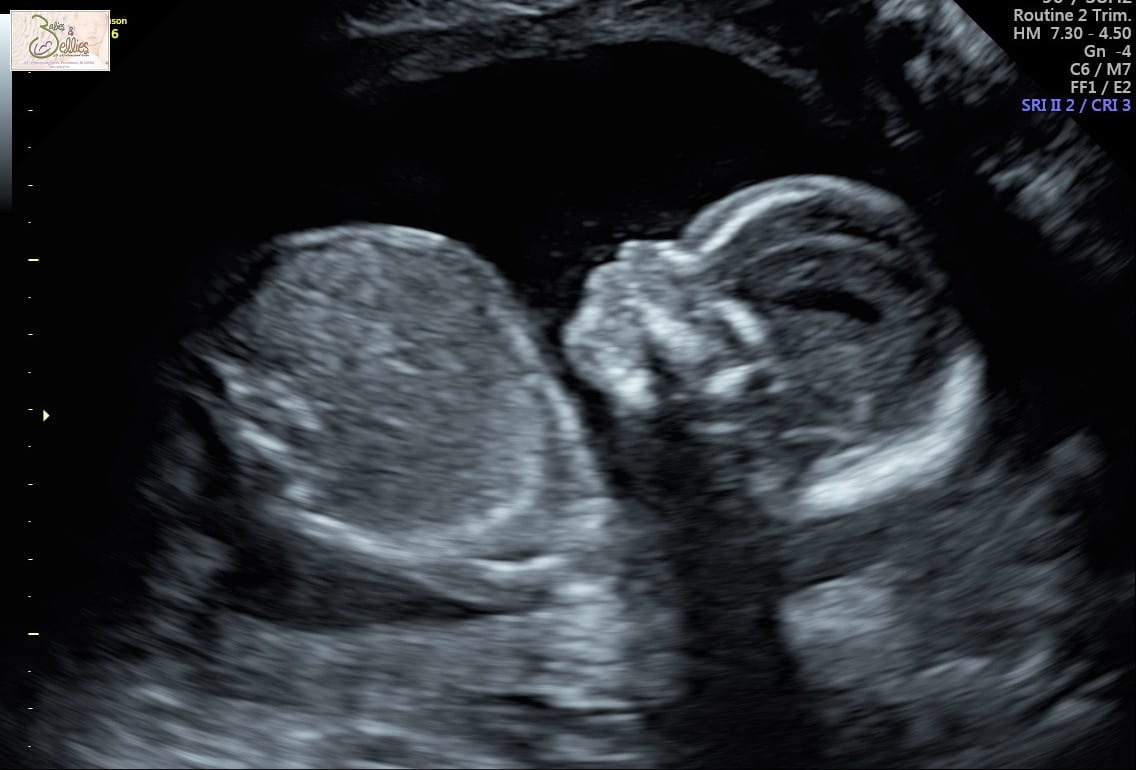

Never in my life did I imagine I would hear the words “I’m so sorry, there’s no heartbeat”. I was certain the Ultrasound Tech was wrong, there was no way… I was pregnant, pregnant for over 9 weeks now. We planned for this baby, talked about names, took pictures for an announcement… we saw a life with this baby… everything was fine.

It was so hard. So hard to understand what just happened. There was no heartbeat and we saw it for ourselves, but I couldn’t believe it. I cried silently, laying there motionless. I wanted to ask her to check it again. We were sent to another room to talk to the OB. I wanted HER to take another ultrasound, but I couldn’t bring myself to ask. She told us how the baby had stopped growing around 6.5 weeks based on measurements. How it was nothing I did or could have done, but likely something in early development of the cells. After discussing our three options, I went home in denial. My body was not recognizing that I was having a miscarriage either. But after two more days at home, acceptance crept in. There was nothing I could do to reverse this, so we said goodbye to our angel baby on January 4th 2019.